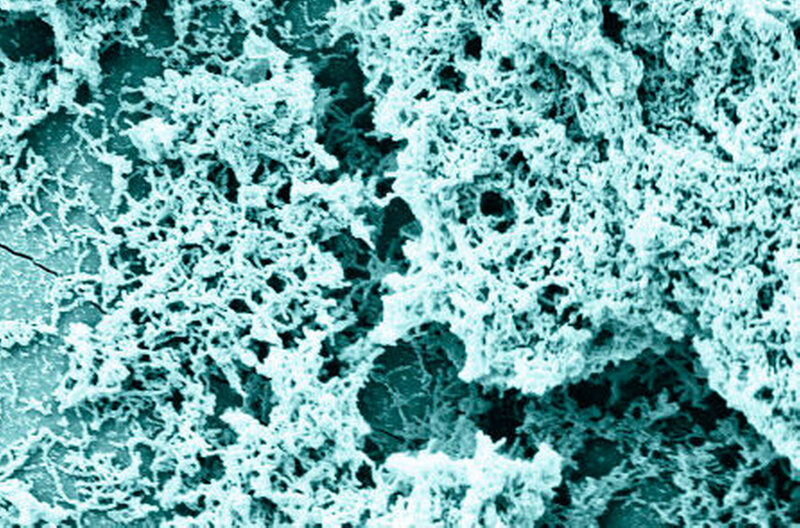

Konsequenterweise gerät die Beeinflussung des kariogenen, mikrobiellen Biofilms zunehmend in den Fokus der Forschung. Auf den ersten Blick würden möglicherweise antimikrobiell wirksame Spüllösungen eine gute Möglichkeit zur Kariesprävention bieten. Im Biofilm leben die kariesauslösenden Bakterien aber in einer Art „Lebensgemeinschaft“, die durch die Anwendung von antimikrobiell wirksamen Substanzen nur sehr bedingt beeinflusst werden kann. Bakterien in Biofilmen können sich nämlich erfolgreich gegen eine derartige Beeinflussung wehren. So sind erheblich höhere Konzentrationen antimikrobieller Wirkstoffe – als in den üblichen Spüllösungen vorhanden – erforderlich, um eine kariespräventive Wirkung zu erzielen.

Auch eine allein mechanische Mundhygiene ohne gleichzeitige Verwendung einer fluoridhaltigen Zahnpasta ist nur begrenzt kariespräventiv wirksam. So verbleibt häufig auch nach dem Zähneputzen an vielen Stellen ein Biofilm auf der Zahnoberfläche, der azidophile und azidurische Keime enthalten kann. Einige Mikroorganismen, die sich in einer sogenannten normalen Mikroflora befinden und mit einer guten oralen Situation korrelieren, sind allerdings in der Lage, Moleküle aus der Nahrung und dem Speichel zu Ammoniak (NH3) zu metabolisieren. Sie halten damit den Biofilm in einer Balance und helfen die Etablierung einer kariogenen Mikroflora zu unterdrücken. Es scheint sogar eine inverse Korrelation zwischen dem Vorhandensein dieser alkaliproduzierenden Mikroorganismen und der Kariesprävalenz zu geben. Der pH-Wert in einem Biofilm auf der Zahnoberfläche wird also unter anderem durch die Produktion von Milchsäure aus niedermolekularen Kohlenhydraten beziehungsweise von NH3aus Proteinen, Peptiden und anderen Molekülen determiniert. Der pH-Wert wiederum bestimmt das Bakterienwachstum und somit auch die Zusammensetzung des Bakterienkollektivs. Umgekehrt wird durch diese Parameter die Pufferkapazität im Biofilm mit beeinflusst.

Deshalb versuchte man bereits in den 1970er Jahren, den Biofilm mit Substanzen zu beeinflussen, die zu einer Pufferwirkung führen und damit den pH-Wert während einer kariogenen Attacke begrenzen. Diese Substanzen müssen von bestimmten Mikroorganismen verstoffwechselt werden, um zum Beispiel Ammoniak als metabolisches Endprodukt zu erhalten. So konnte gezeigt werden, dass die Produktion alkalischer Metaboliten beim oralen Biofilm eine wichtige Rolle für die Kariesprävention spielt, weil die Säuren in der Plaque gepuffert werden und daraus eine wenig kariogene Flora resultiert (Abbildung 2). Damit könnte eine neue Strategie gefunden sein, die die Mundgesundheit fördert. Aufgrund der grundlegenden Untersuchungen von Kleinberg et al. wurde zum Beispiel Arginin als eine derartige Substanz identifiziert. Arginin ist in freier Form im Speichel (50 µmol) und gebunden an Speichelproteine und -peptide vorhanden.